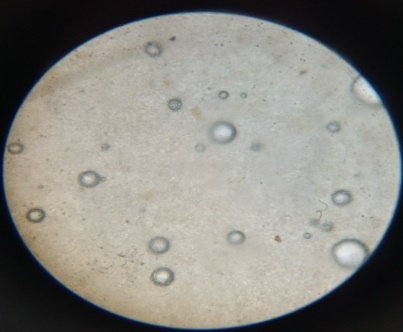

Optical microscopy

The proniosomal orabaseand drug orabasewas placed on a glass slide and observed for vesicles using a compound microscope under 100X magnification; magnified images were captured.

The size of the formed vesicles has a major contribution towards in vivo fate. From (fig. 2) it is observed that the shape of proniosomal (F(ACL)1-F(ACL)4) formulations exhibited, following hydration yields niosomes with spherical morphology on 100X magnification.

Fig.2: Optical microscopic images of proniosomal formulationsA) F1(Span60)B)F2(Span40) C) F3(Span20) D) F4(Span80)at 100X magnification

From (fig. 6) it is observed that the shape of proniosomal orabase formulation exhibited spherical morphology at 100X magnification.The proniosomal orabase formulation system exhibited abundant vesicle formation in contrast to drug orabase.

Fig.6: Optical microscopic images of proniosomal and drug orabase formulationsA) Proniosomal Orabase B) Drug orabase at 100X magnification